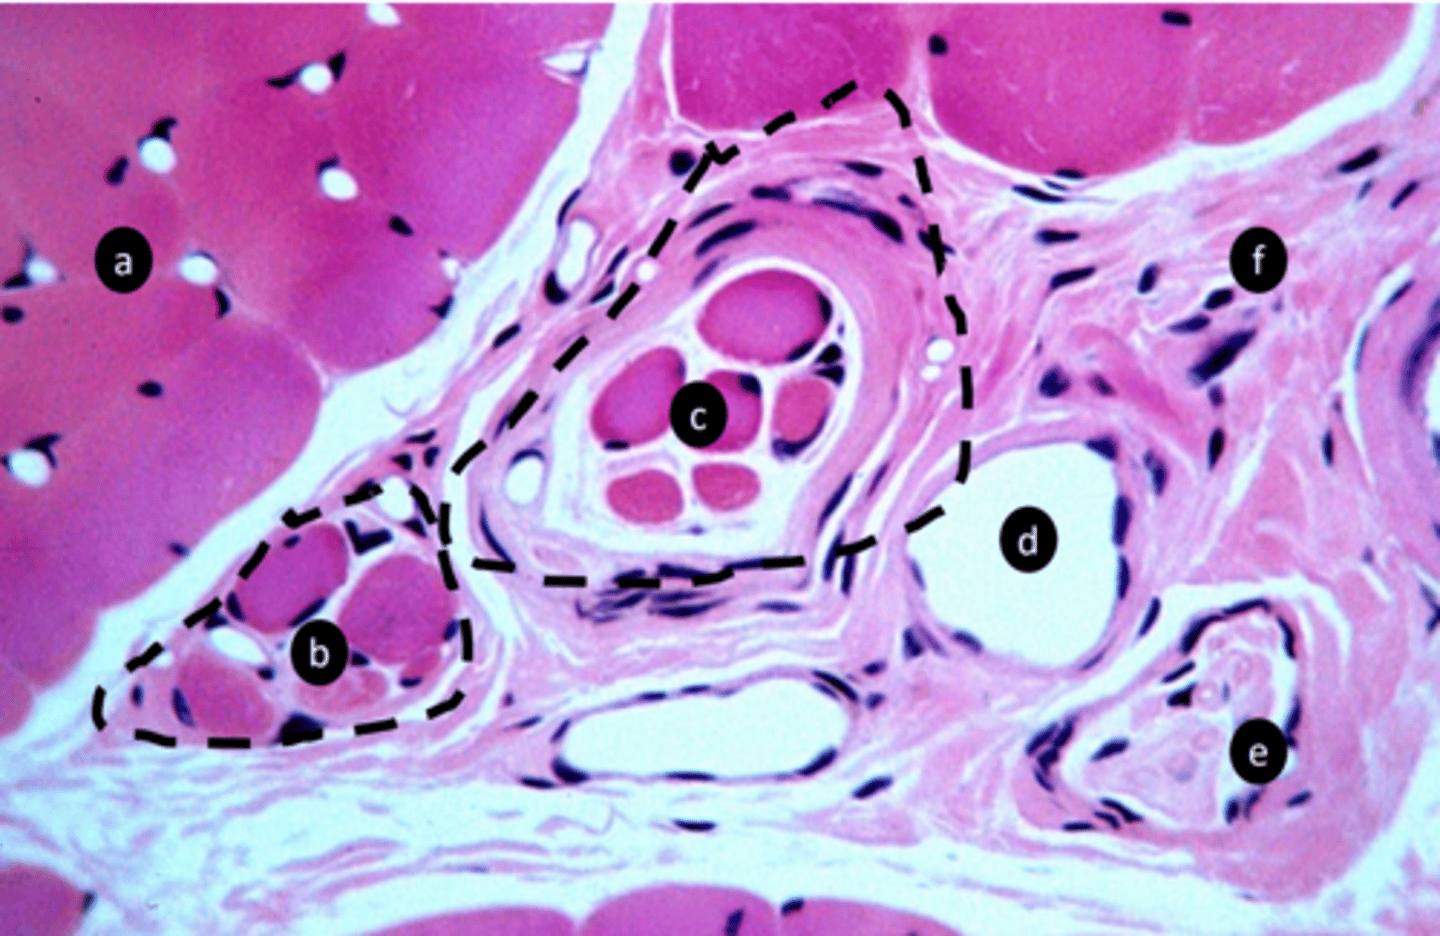

5

New cards

vein

e: structure

<p>e: structure</p>

6

nerve fibers

f: structure

<p>f: structure</p>

7

CT

g: tissue type

<p>g: tissue type</p>